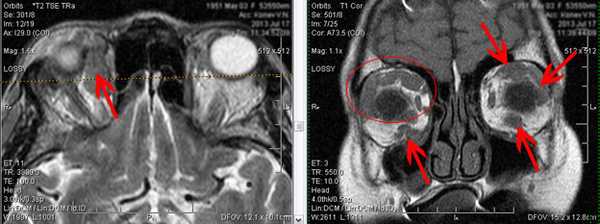

7. Ретинит, вызванный цитомегаловирусом.

Аксиальное Т1-взвешенное изображение с контрастным усилением: асимметричное утолщение сосудистой оболочки глаза справа (стрелка) по сравнению с левой стороной.

8. Каротидная кавернозная фистула.

На аксиальной Т1-взвешенной МР-томограмме визуализируется расширение правой и левой верхних глазничных вен (стрелки).

9. Тромбоз верхней глазничной вены.

Корональная Т1-взвешенная МР-томограмма демонстрирует гиперинтенсивный сигнал в проекции расширенной левой верхней глазничной вены (стрелка), свидетельствующий о тромбозе. Маленькая стрелка указывает на смещенный влево зрительный нерв.